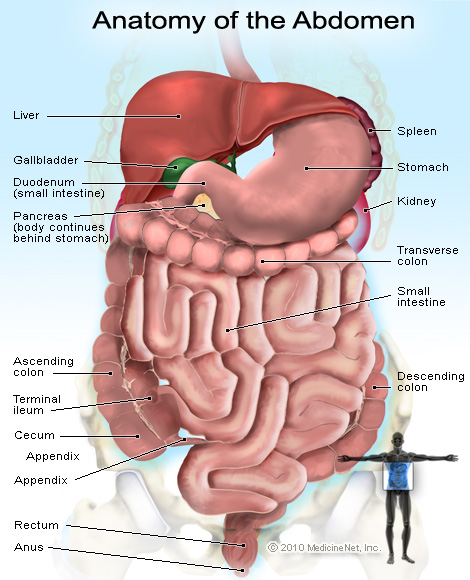

Female Abdominal Anatomy Images . Female Abdominal Anatomy Images …

Female Abdominal Anatomy Pictures – koibana.info | Anatomy organs …

Pin on Abdominal Pain

Causes of Pain in the Right Side | New Health Advisor

right lower abdomen body organs

What Can Cause Right Side Abdominal Pain?

Abdominal and Pelvic Pain in the Nonpregnant Female | Tintinalli’s …

Lower Abdominal Pain: Symptoms And Causes – Forbes Health

Abdominal pain | Health | Pinterest | Pain d’epices and Abdominal pain

Female Abdominal Pain | Types | Symptoms | Causes | Diagnosis | Treatment

What Is Pain In Lower Right Side Of Stomach – StomachGuide.net